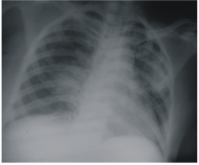

Chest Radiographic Patterns in HIV Associated Kaposi's Sarcoma in Benin City, Nigeria

DOI: https://doi.org/10.82235/wajr.vol18no1.212